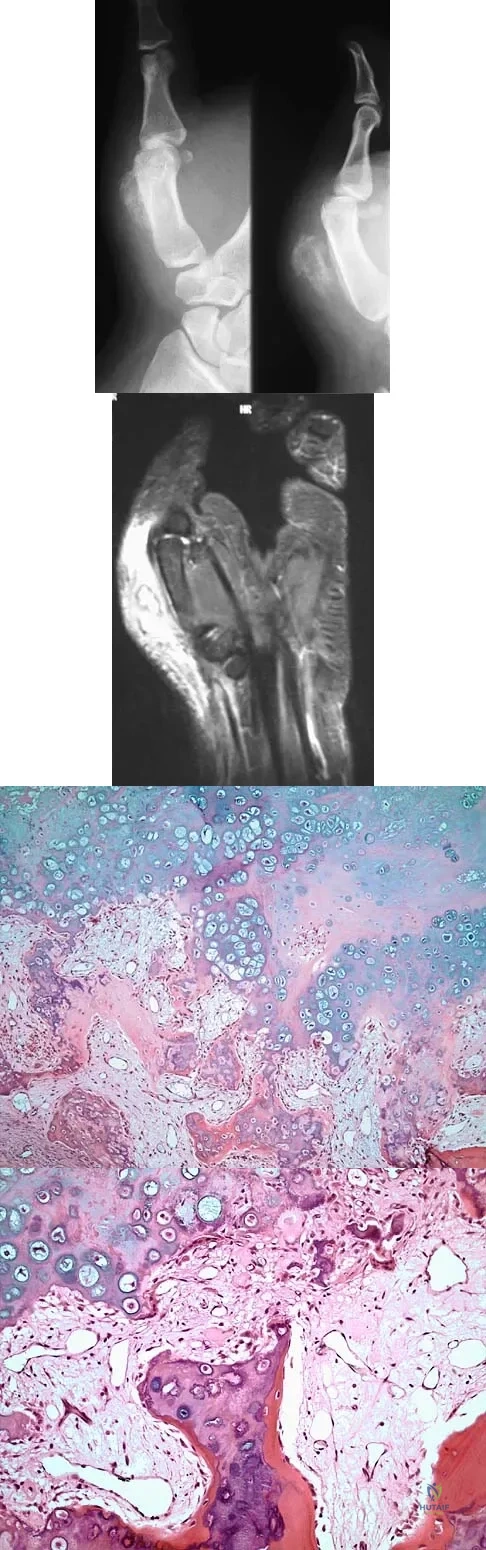

A 19-year-old girl has had pain and swelling in the right ankle for the past 4 months. She denies any history of trauma. Examination reveals a small soft-tissue mass over the anterior aspect of the ankle and slight pain with range of motion of the ankle joint. The examination is otherwise unremarkable. A radiograph and MRI scan are shown in Figures 45a and 45b, and biopsy specimens are shown in Figures 45c and 45d. What is the most likely diagnosis?

Explanation